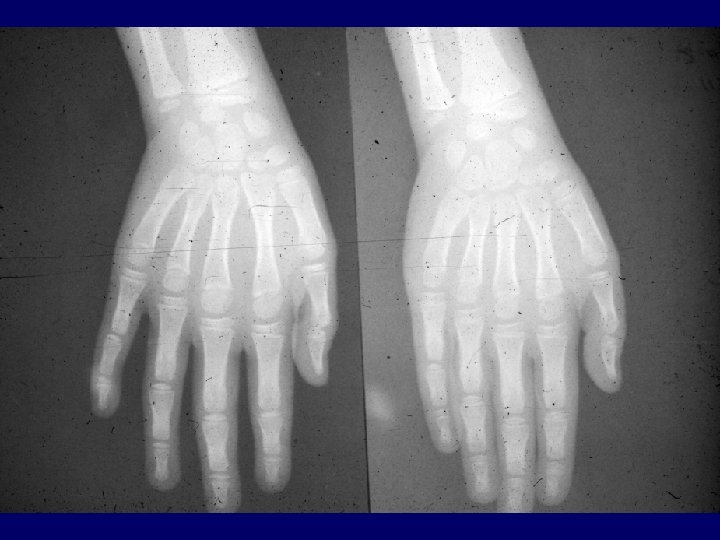

Brain CT hypodense lesions related to the spongy leukoencephalopathy Brain MRI data is sparse Skeletal Muscle Biopsy shows in almost all patients with KSS typical ragged-red fibers Heart muscle has no ragged-red fibers There is no histopathological difference between KSS and PEO in muscle biopsy specimens

Mitochondrial Dysfunction Serum lactate level pre and post exercise Brain CT or MRI for spongy leukoencephalopathy Skeletal muscle biopsy for histochemistry, electromicroscopy for detection of raggedred fibers Skeletal muscle biopsy or blood for examination for mt. DNA deletions